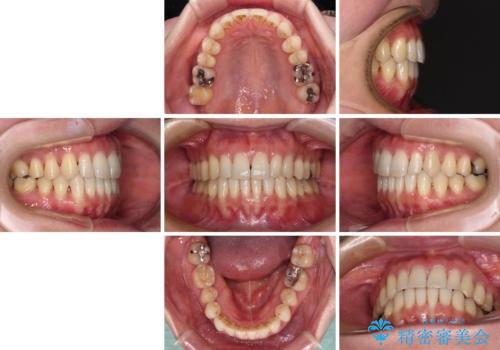

- 下顎の八重歯と、上下のクロスバイトを気にして来院された患者様です。

インビザラインを用い、下顎全体の後方移動、IPR(歯と歯の間を削る)と歯列全体を拡大させることで、歯並びを整えていくこととしました。

奥に位置していた上の前歯が下の前歯を乗り越える際、奥歯でものを咬むことができず、辛い時期が続きました。